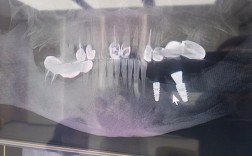

- 大剂量化疗或联合放疗:若化疗期间或结束后需行头颈部放疗,种植需推迟至放疗结束后6-12个月(放疗会导致骨微循环破坏,骨坏死风险更高),且需通过CBCT评估骨密度及血供情况;

| 口腔局部评估 | CBCT/全景片(测量骨高度、厚度、密度)、牙周检查(探诊出血、牙周袋深度) | 评估骨量是否充足、有无牙周炎等基础疾病 |